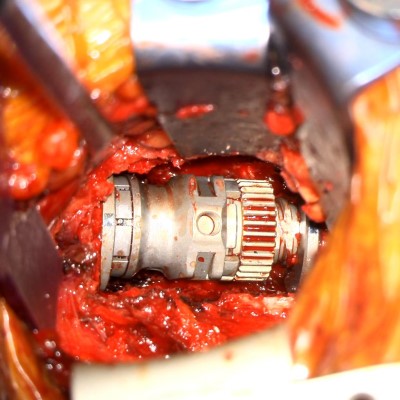

Intraoperative fluoroscopic images (lateral projections) taken during the C7 corpectomy and fusion procedure. Left image shows localizing needle in the C7-T1 disc space. Right images show the expandable interbody biomechanical device (aka cage) being applied. The upper image shows the top of the cage while the lower image shows the bottom.

- Intra-op